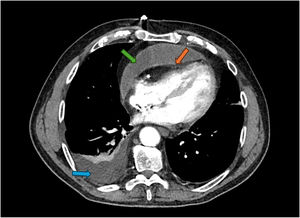

- Atresia pulmonar con septo interventricular intacto

- Alejandro Fernández-Cisneros, Bosco A. Moscoso, Stefano Congiu

- Rev Esp Cardiol. 2025;78:1020-1